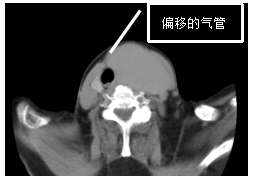

B超检查提示胡奶奶得的是

“甲状腺双叶结节”

肿瘤近10厘米大小,气管明显偏移